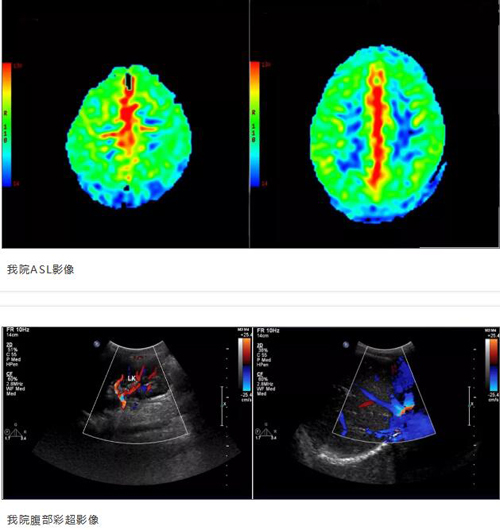

入院后完善相关检查,ASL检查提示双侧额顶叶、纵裂池内多发条状高灌注;腹部彩超提示脾大,余未见明显异常。